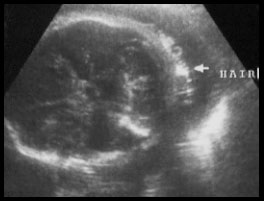

This is a shot of her hair.                        This picture is a lot like the one

The tech says she has lots of it.                            I posted for 27wks.